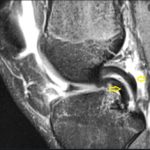

Image Challenge 11, #Oncology

24 year old man presented with pain and swelling in the knee for the past 3 months. Popular Answer may not imply right answer, follow our twitter handle for the right answer, www.twitter.com/drhiteshg Write your comments and explanations in the section below.